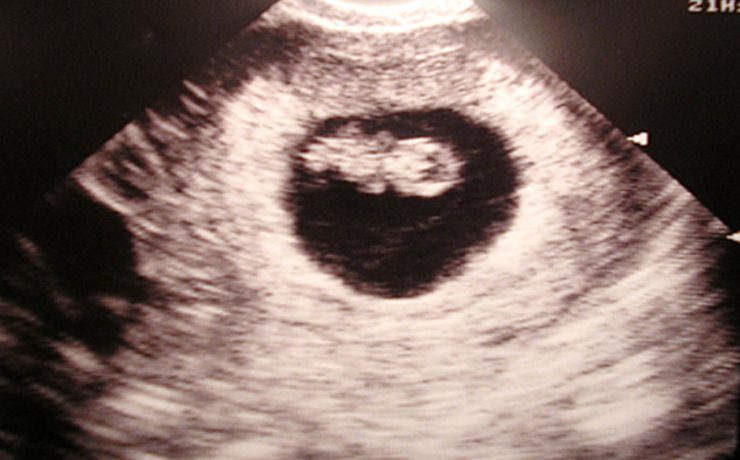

Defectos de la pared abdominal. Estudio comparativo entre onfalocele y gastrosquisis

El onfalocele y la gastrosquisis son los defectos de la pared abdominal, de tamaño variable, que se ubica en directa relación con el cordón umbilical, que contiene asas intestinales y a veces otros órganos como parte del hígado, recubiertos por amnios en la superficie externa, peritoneo en la superficie interna,